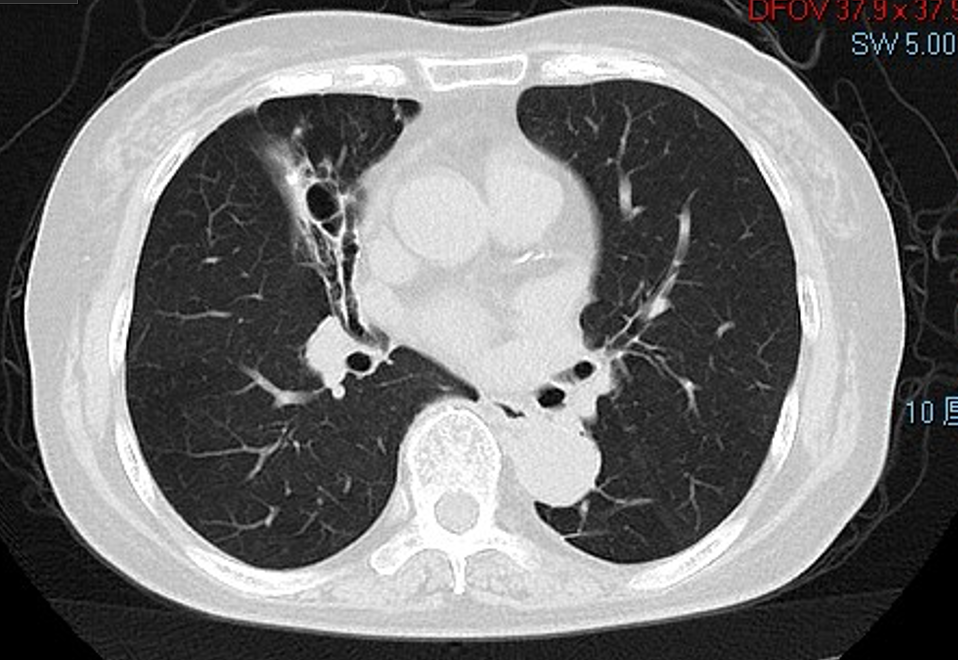

胸部CT(2021-2-23)